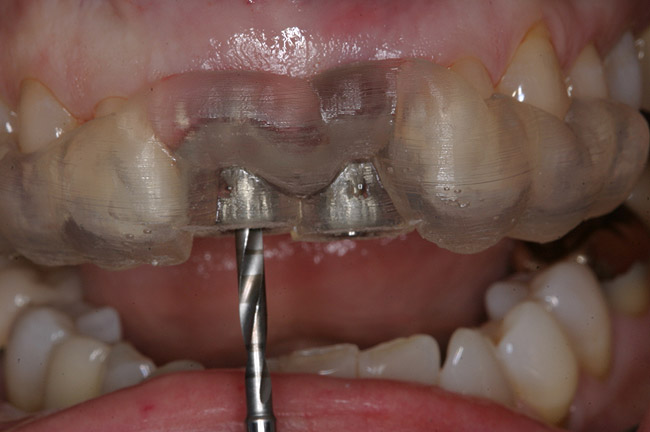

Figure 13   CT-derived fabrication of a surgical guide enabled proper fixture placement into the fresh extraction sockets.

Figure 13